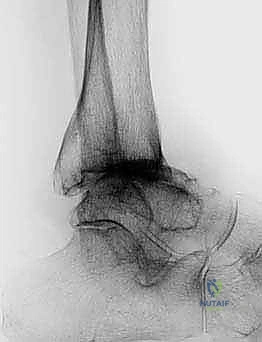

الأسباب العميقة وعوامل الخطر لخشونة الكاحل المتقدمة

على عكس مفصلي الركبة والورك، حيث تكون الخشونة الأولية (بسبب التقدم في العمر والاستهلاك الطبيعي) هي السبب الشائع، فإن خشونة مفصل الكاحل لها طبيعة مختلفة تماماً. الغالبية العظمى من حالات تآكل مفصل الكاحل هي نتيجة لإصابات سابقة أو أمراض جهازية.

1. خشونة الكاحل ما بعد الصدمة (Post-Traumatic Osteoarthritis)

يمثل هذا النوع حوالي 70% إلى 80% من جميع حالات خشونة الكاحل. يحدث عندما يتعرض المفصل لإصابة تؤدي إلى تلف ميكانيكي مباشر للغضروف أو تغير في استقامة العظام.

* كسور الكاحل المعقدة: الكسور التي تشمل السطح المفصلي (Pilon fractures أو Malleolar fractures) تترك ندبات على الغضروف وتغير من توزيع الوزن.

* الالتواءات المتكررة (Chronic Instability): تمزق الأربطة المتكرر يؤدي إلى عدم استقرار المفصل، مما يسبب حركات غير طبيعية (Micro-trauma) تدمر الغضروف تدريجياً بمرور السنوات.

* سوء الالتئام (Malunions): إذا التأم كسر سابق في الساق أو الكاحل بزاوية غير صحيحة، فإن ذلك ينقل قوى الوزن إلى مناطق صغيرة من الغضروف غير مهيأة لتحمل هذا الضغط، مما يسرع من تآكلها.

2. التهاب المفاصل الروماتويدي (Rheumatoid Arthritis)

هو مرض مناعي ذاتي يقوم فيه جهاز المناعة بمهاجمة الغشاء الزليلي (Synovial membrane) المبطن للمفصل. يؤدي هذا الالتهاب المزمن إلى إفراز إنزيمات تدمر الغضروف والعظام المجاورة. المرضى الذين يعانون من الروماتويد غالباً ما يصابون بتشوهات شديدة في الكاحل والقدم، ويُعد استبدال المفصل حلاً ممتازاً لهم للحفاظ على حركيتهم.

الأعراض السريرية: متى يجب التفكير في الجراحة؟

المرضى الذين يصلون إلى عيادة الأستاذ الدكتور محمد هطيف غالباً ما يعانون من تاريخ طويل من الألم الذي يستنزف طاقتهم. تشمل الأعراض الرئيسية التي تشير إلى الحاجة المحتملة لاستبدال مفصل الكاحل ما يلي:

- ألم مبرح ومستمر: ألم عميق في الكاحل يزداد سوءاً مع تحمل الوزن، المشي، أو حتى الوقوف لفترات قصيرة. في المراحل المتقدمة، قد يوقظ الألم المريض من نومه (ألم الراحة).

- تيبس شديد وفقدان نطاق الحركة: صعوبة بالغة في ثني القدم لأعلى (Dorsiflexion) أو لأسفل (Plantarflexion)، مما يؤثر بشكل مباشر على نمط المشي ويجعل صعود ونزول السلالم تحدياً كبيراً.

- تورم مزمن: انتفاخ دائم حول المفصل لا يزول تماماً مع الراحة أو رفع القدم.

- العرج (Limping): تغير ملحوظ في طريقة المشي لمحاولة تجنب وضع الوزن على الكاحل المصاب، مما قد يؤدي لاحقاً إلى آلام في الركبة، الورك، وأسفل الظهر.

- أصوات طقطقة أو احتكاك (Crepitus): شعور أو سماع صوت طحن داخل المفصل عند تحريكه، ناتج عن احتكاك العظام العارية ببعضها.

التشخيص الدقيق: نهج الأستاذ الدكتور محمد هطيف

يبدأ التقييم الطبي الشامل بأخذ تاريخ مرضي دقيق وفحص سريري مفصل. يقوم الدكتور هطيف بتقييم نطاق الحركة، قوة العضلات، استقامة القدم والكاحل، وحالة الدورة الدموية والأعصاب الطرفية.

تُعد الأمانة الطبية الصارمة ركيزة أساسية في ممارسة الدكتور هطيف؛ فهو لا يتخذ قرار الجراحة إلا بعد استنفاد كافة سبل التقييم الدقيق. يعتمد التشخيص على أحدث تقنيات التصوير الطبي:

* الأشعة السينية أثناء الوقوف (Weight-bearing X-rays): هي المعيار الذهبي لتقييم تضيق المسافة المفصلية، وجود النتوءات العظمية، وتحديد درجة التشوه (Varus/Valgus).